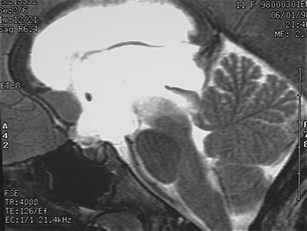

The sylvian aqueduct is the most common site of intraventricular blockage of the cerebro-spinal fluid. Clinical aspects, neuroradiological appearance, and treatment of hydrocephalus secondary to aqueductal stenosis are specific.

The correct interpretation of the modern neuroradiologic techniques may help in selecting adequate treatment between the two main options (third ventriculostomy or shunting). In the last decades, endoscopic third ventriculostomy has become the first-line treatment of aqueductal stenosis; however, some issues, such as the cause of failures in well selected patients, long-term outcome in infant treated with ETV, and effect of persistent ventriculomegaly on neuropsychological developmental, remain unanswered.